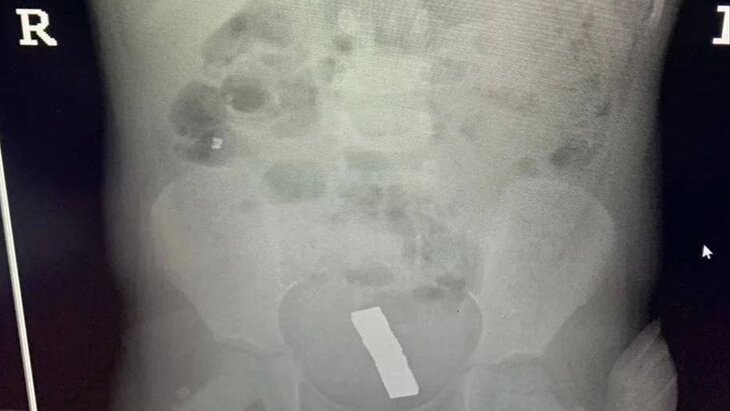

Ребенка госпитализировали с жалобами на боли в животе. После обследования в кишечнике обнаружили магниты.

Он отметил, что из-за сильного магнитного притяжения шарики вызвали образование отверстия в кишечнике, которое врачи зашили после удаления инородных тел. Пять шариков успели переместиться в малый таз.